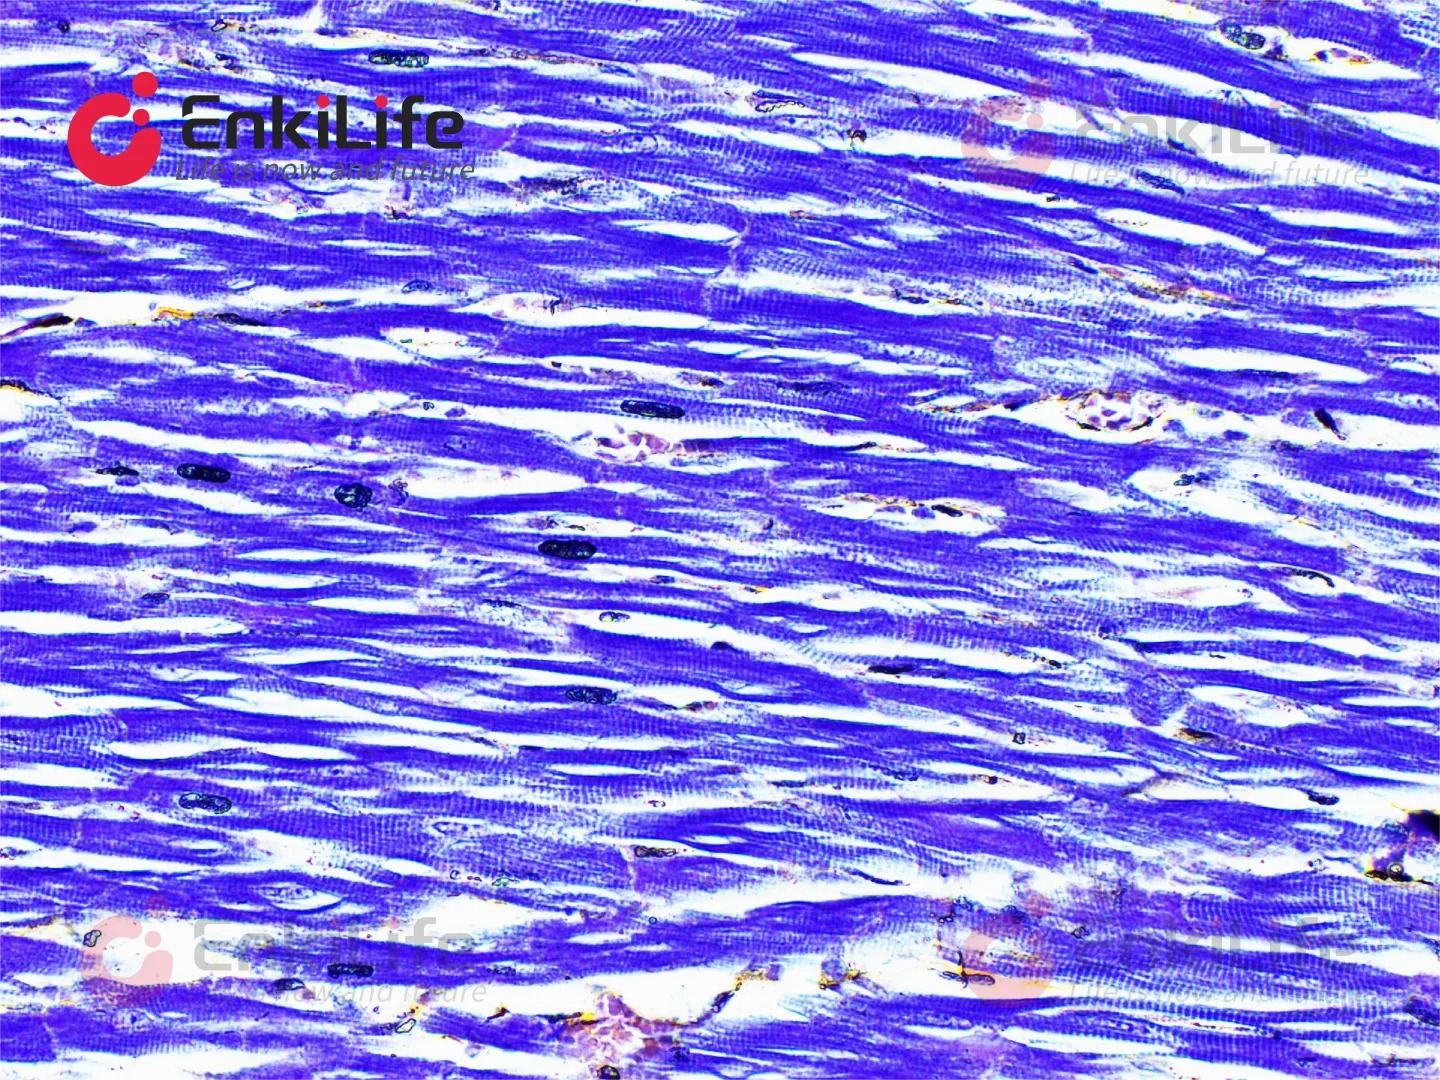

三、染色效果??

经过磷钨酸苏木素染色的切片,肌肉纤维会呈现出一种美丽的紫蓝色,就像是一条条精致的丝带,清晰地排列在组织中。神经纤维也会被染上淡淡的蓝色,和周围的组织形成鲜明的对比。而且这种染色方法还能显示出一些特殊的结构,比如肌肉中的横纹,这对于科研分析来说可是超级重要的线索呢。